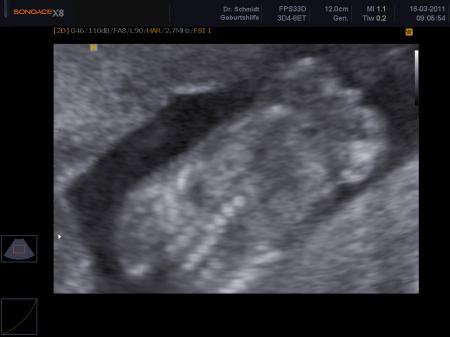

Huhu .. Ja ich bin auch sehr verwirrt. Zumal ich von 4 verschiedenen Ärzten gesagt bekommen habe das es ein Junge wird. Meine FÄ schaute nun mehrfach hin aber das Kleine lag recht ungünstig. Sie meinte aber die Schamlippen erkennen zu können und das eindeutig ein Mädchen sei. Den nächsten US hab ich in 2 Monaten. Nächten Monat ist ein normaler Termin, ohne US und danach dann wieder mit. Ich bin mir sehr unsicher .. vom Gefühl her kann ich nun gar nix mehr sagen. Ich trau mich nichtmal was zu kaufen, auser es würde für beide Geschlechter passen^^ Was war bei dir der Grund das man dachte es sei ein Mädchen? Bei mir sagte man das das erste mal die Nabelschnur im weg sei. Hier mal ein Bild wo es hieß, das is eindeutig ein Junge. Da war ich in der 17 SSW und oben Rechts soll das Zippel sein. Ich hatte damals mehr als 3 Aufnahmen und auch beim US eine klare sicht und es war selbst für mich als Leie eindeutig. Ich wäre nie drauf gekommen das das die Nabelschnur sein könnte.